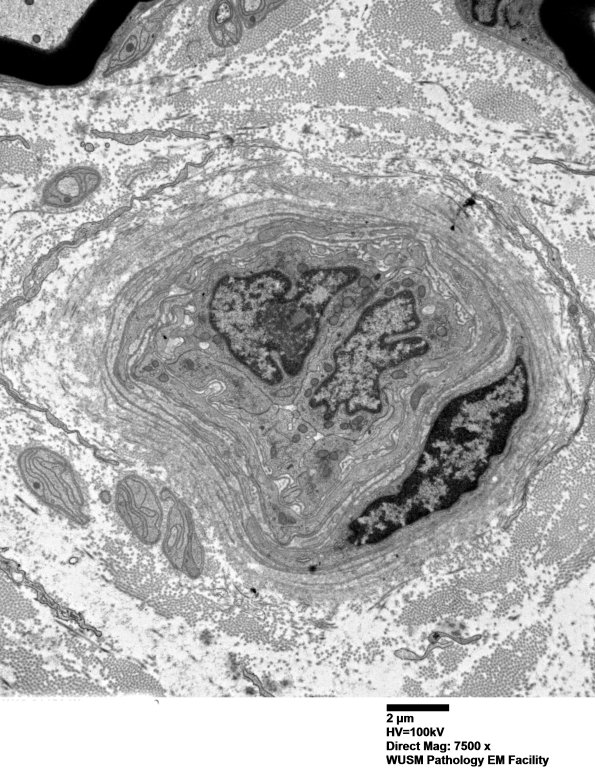

Washington University Experience | VASCULAR | Hypoxia-Ischemia, fetal-neonatal | White Matter | 16B4 (Case 16) HIEM EM019 - Copy

16B4 (Case 16) HIEM EM019 - Copy